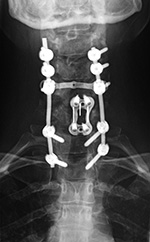

Cervical spine anterior and posterior fusion Cervical spine anterior and posterior fusion with intervertebral bone struts (plugs)

Anterior and posterior cervical spine fusion AP view Anterior and posterior cervical spine fusion lateral view Anterior and cervical spine fusion with intervertebral bone struts Anterior and cervical spine fusion with intervertebral bone struts

Young woman with traumatic locked facets at C6-7 and C7 body fracture. A posterior cervical fusion with lateral mass screws (cervical spine) and pedicle screws (thoracic spine) and rods extends from C4 to T2. There is an anterior cervical fusion plate and screws at C6-7 with a intervertebral disk cage at C6-7 and a crosslink at C6. There is an anterior cervical fusion plate that extends from C3 to C7 and posterior lateral mass screws and rods on each side from C3 to C7. Intervertebral bone struts (plugs) are present at the disk spaces from C3 to C6.